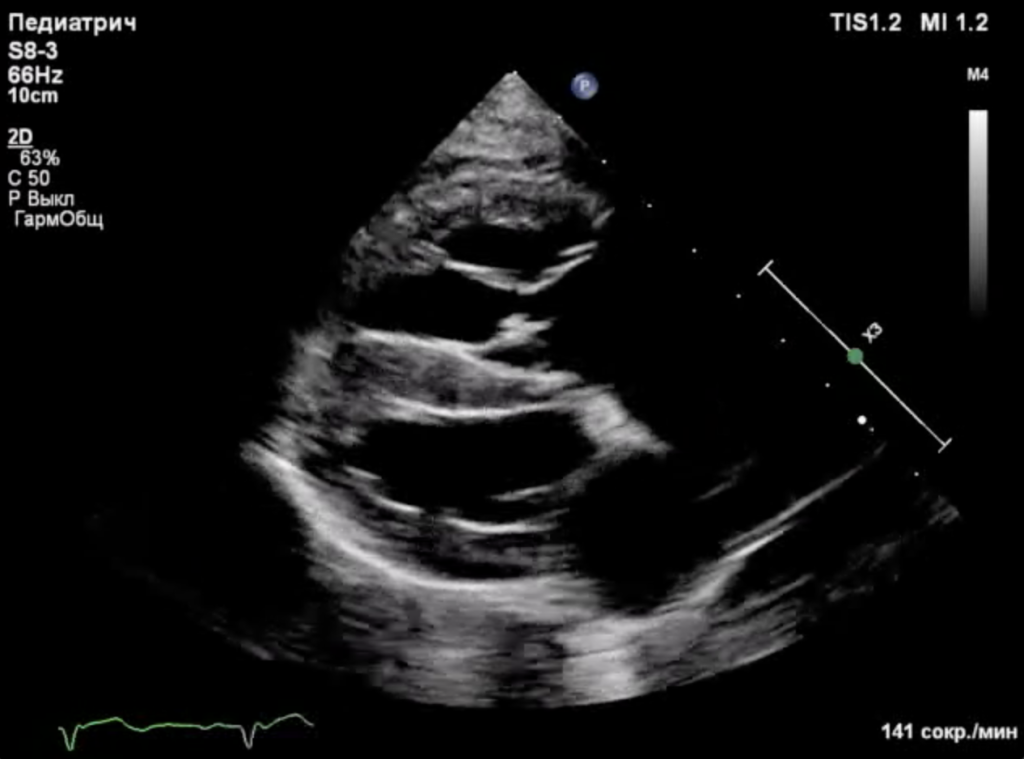

Собака находилась под наблюдением с 5-месячного возраста. При эхокардиографическом исследовании были выявлены следующие аномалии (фото 1-3):

- Выраженная дилатация правого предсердия (47 мм) и правого желудочка (конечный диастолический размер – 34 мм).

- Неделаминированная и малоподвижная септальная створка.

- Укороченные хорды.

- Выраженная регургитация (massive).

- Гепатомегалия, обусловленная застоем крови в системных венах.